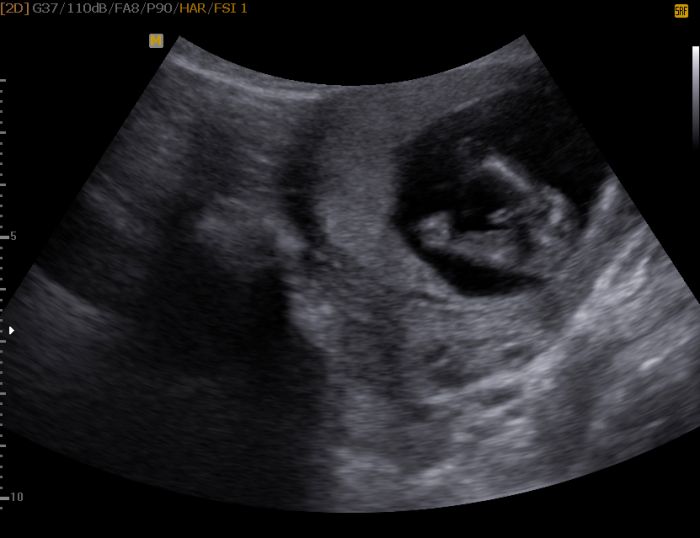

Už by to mohlo být vidět, když se špunt dobře natočí. Mě to dr. řekla ve 14.týdnu s tím, že mi to ještě potvrdí na kontole za měsíc, kam jdu 3.října. A vzhledem k tomu, že to, co plandá mezi nožičkama vypadá dost sugestivně, tak se verze asi měnit už nebude